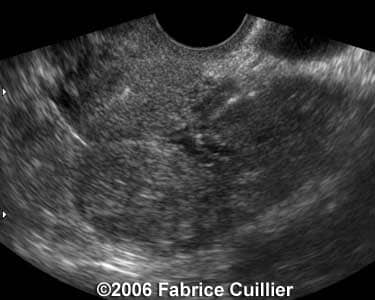

These are some cases of ectopic pregnancy (GEU) using the 2D and 3D scans.

Case 2